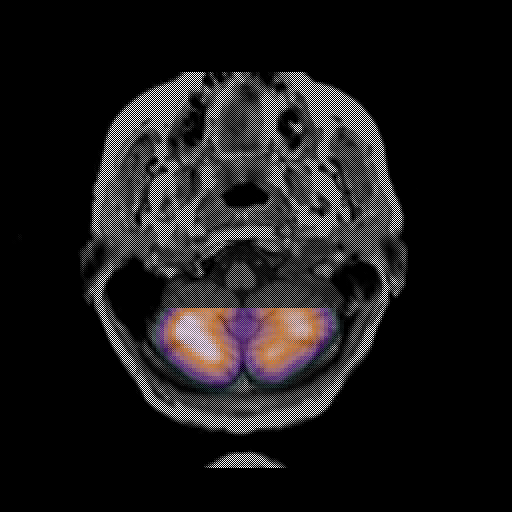

overlay: Slice 7

Slice 7

MRCBFCBF with

T1PDT2T1PDT2